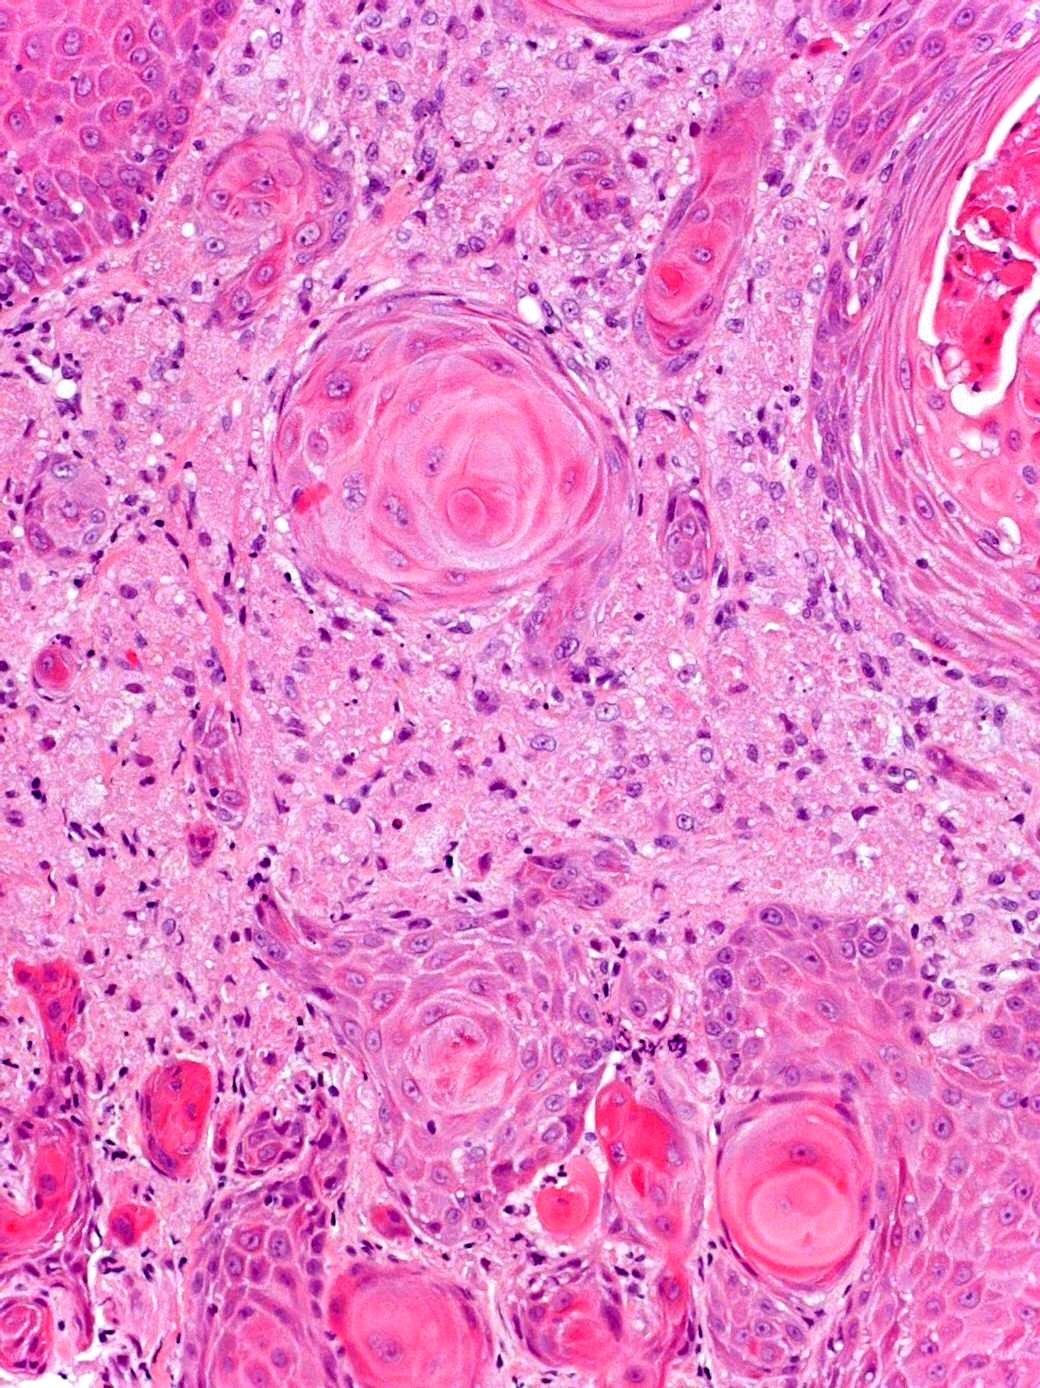

Adenoid cystic carcinoma

 Wide age range

 Slow growing with tendency for perineural spread

 Tubular, cribriform and solid patterns

 2 cell populations: ductal cells and abluminal myoepithelial cells

 Cytologically bland, angular and dense chromatin

 Cribriform pattern: multiple punched out holes “pseudocysts”

 Contain dense eosinophilic basement membrane-like material or bluish mucopolysaccharides

 Perineural invasion +++

 5 yr survival good, 20 yrs <10%

 Lung metastases seen later in course